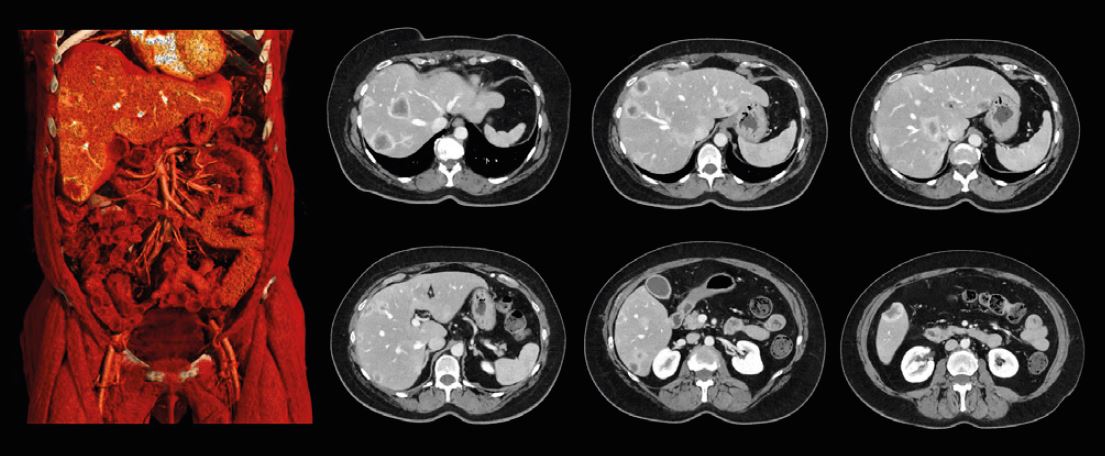

Зображення черевної порожнини, реконструйовані за допомогою різних алгоритмів реконструкції на зрізах товщиною 0,5 мм

Зображення черевної порожнини з PIQE 1024 товщиною зрізу 0,5 мм демонструють підвищену просторову роздільну здатність у цього пацієнта з ураженням печінки.

Precise IQ Engine (PIQE)

Це алгоритм реконструкції

глибокого навчання, який

максимізує власну роздільну

здатність комп’ютерної

томографії для отримання

матричних зображень

суперроздільності 1024.

Зображення PIQE показують

чіткіші анатомічні деталі

для кращого окреслення

невеликих анатомічних

структур для більш точного

діагнозу.